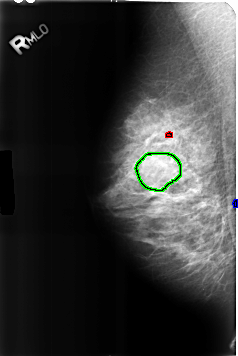

FILE: B_3226_1.RIGHT_MLO.OVERLAY TOTAL_ABNORMALITIES 3 ABNORMALITY 1 LESION_TYPE CALCIFICATION TYPE COARSE DISTRIBUTION N/A ASSESSMENT 2 SUBTLETY 3 PATHOLOGY BENIGN_WITHOUT_CALLBACK TOTAL_OUTLINES 1 BOUNDARY ABNORMALITY 2 LESION_TYPE MASS SHAPE OVAL MARGINS CIRCUMSCRIBED-OBSCURED ASSESSMENT 2 SUBTLETY 3 PATHOLOGY BENIGN TOTAL_OUTLINES 1 BOUNDARY ABNORMALITY 3 LESION_TYPE CALCIFICATION TYPE COARSE DISTRIBUTION N/A ASSESSMENT 2 SUBTLETY 3 PATHOLOGY BENIGN_WITHOUT_CALLBACK TOTAL_OUTLINES 1 BOUNDARY |